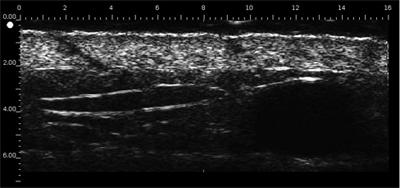

DERMCUP permite la adquisición no invasiva de secciones verticales de la piel in vivo

La dermis es ecogénica. Los ecos provienen de la red de fibras de colágeno y fibras elásticas. En relación a la dermis, las lesiones (tumores, quistes, angiomas …) aparecen como áreas hipoecoicas.

Sonda 2D Muy ergonómica  Fácilmente manipulada  Adquisición de 10 imágenes / s

Adquisición de sonda 3D de 300 imágenes 2D.